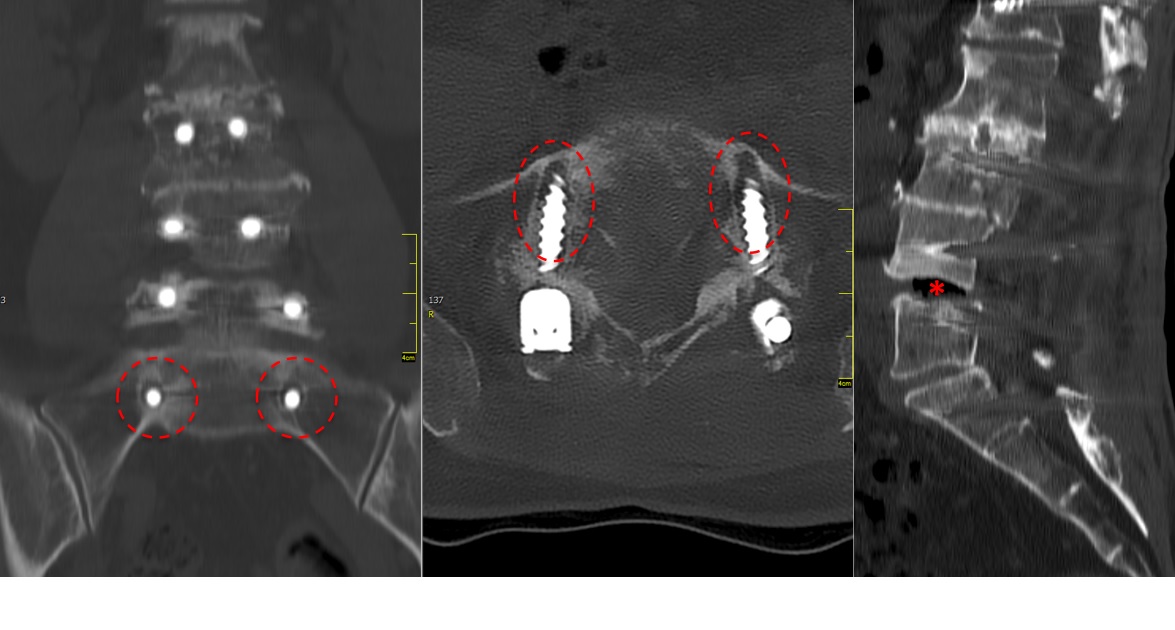

A CT scan allowed a more detailed assessment (Fig 7). There was an obvious nonunion at L5/S1, with loose screws in the sacrum (red circle). Furthermore, there was instability at L4/L5 as the intervertebral disc presented with an important vacuum phenomenon (asterisk). Foraminal stenosis at L5/S1 (not shown) seemed to be the reason behind the persistent leg pain.

The treatment plan was an anterior height restoration and fusion of L5/S1 and L4/L5. A posterior revision surgery was not considered due to the wide decompression and obvious scar formation. For the correction of level L4/L5, an oblique anterolateral approach (OLIF) was selected due to considerable calcification of the aorta and the iliac vessels. At the L5/S1 level, a straight anterior approach was selected and an additional plate fixation (ATB) was performed.

At level L5/S1, a large cage with an angulation of 14 was selected and for L4/L5, a large cage with an angulation of 10 was placed. In order to perform a fusion, the cages were each filled with 6 mg of BMPII.

From six months postoperatively, leg discomfort decreased. Within an additional four months, pain disappeared completely and both foot and hip weakness recovered. The back pain persists to a certain extent but is not impedingthe patient in her daily activities. The x-ray taken 10 months after the anterior revision surgery revealed a complete and solid fusion on both levels (Fig 8). This is confirmed by the appearance of dense bone in the radiolucentcage.